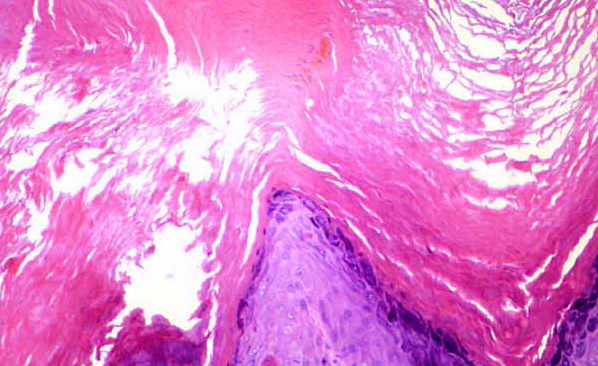

Read MoreParakeratosis in Normal Oral Mucosa =نظير التقرن في المخاطية الطبيعية